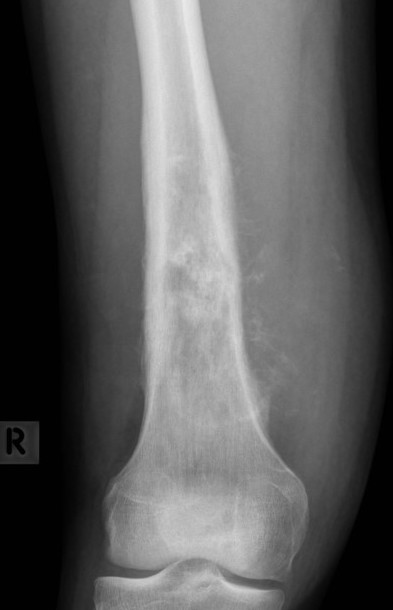

Osteosarcoma of the distal femur

Osteosarcomas of the proximal tibia

Xray

Typically metaphysis of long bones

- distal femur 35%

- proximal tibia 20%

Features

- new bone formation / osteoid

- permeative cortical destruction

- wide zone of transition

- periosteal reaction

- soft tissue mass